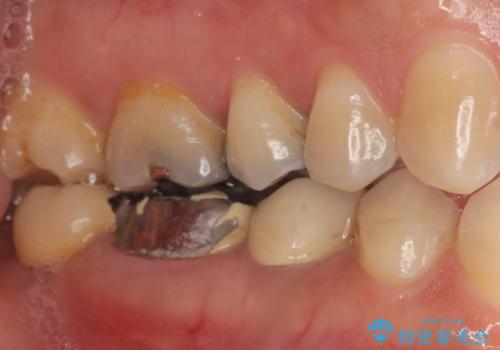

- 奥歯の痛みを主訴に来院された患者様です。

精査したところ、右下の奥歯(右下6)は割れており保存不可能な状態でした。

患者様のご希望により、右下大臼歯2本(右下76)のインプラント治療、右下小臼歯(右下5)の根管治療及び補綴治療を行いました。

割れていた歯の周囲組織の炎症が強く、骨の厚みが薄かったため、インプラント埋入時に骨増生(GBR)を行いました。